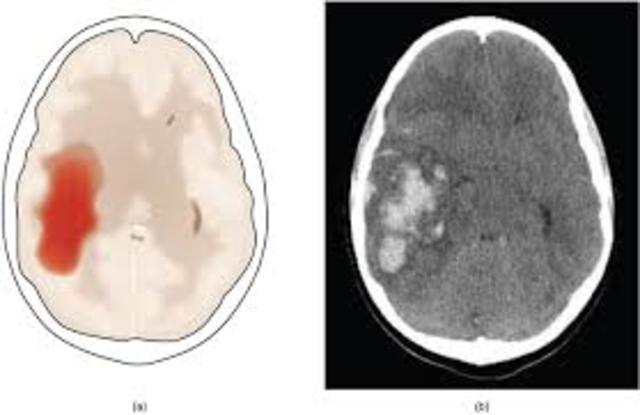

se define como una reducción, o ausencia completa de la irrigación sanguínea puede ser: Isquemia Global: , cuando el flujo sanguíneo es insuficiente para cubrir las demandas metabólicas del cerebro, causado por un paro cardíaco, una isquemia prolongada conduce al infarto. Isquemia Focal:se produce cuando un coágulo de sangre ha ocluido un vaso cerebral lo que reduce el flujo de sangre a una región específica aumentando el riesgo de muerte celular, causada por trombosis o embolia

1.-Infarto en Divisoria de Aguas

ubicado en Zonas vulnerables situadas entre territorios irrigados por las arterias cerebrales mayores. (A. Media, Anterior y Posterior)

La Hipotension marcada: La irrigación sanguínea de zonas distales disminuye, lo que predispone a la isquemia y al infarto de los tejidos. si se restablece el flujo sanguíneo adecuado inicia la recuperación funcional de áreas de corteza pero los infartos que se presentan en esta zona provocan déficit neurológico local.